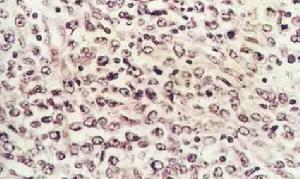

淋巴母細胞 1.大細胞淋巴瘤 大細胞淋巴瘤有時也稱硬化性瀰漫性大細胞淋巴瘤,近年來套用表型及基因探針技術追蹤其來源和分化,證單一的大細胞組成。細胞大,胞質豐富,核呈圓形或卵圓形,染色質明顯而分散核仁突出。機化性硬化較少,可能與腫瘤壞死有關。

(1)T細胞免疫母細胞肉瘤:表現出更多的外周T細胞淋巴瘤的特徵。細胞表現為多形性,從體積小核捲曲的淋巴樣細胞到大細胞都有,大細胞胞質豐富,大而分葉的細胞核,核仁明顯。基質富含毛細血管後小靜脈有明顯的細小網狀膠原纖維,機化性硬化雖然不很明顯,見不到濾泡中心細胞淋巴瘤所具有的粗大的互相交錯結合的纖維束。T細胞免疫母細胞肉瘤可表達高分化T細胞抗原,但不表達TdT(早期表現型),這一點與淋巴母細胞瘤正相反

2.淋巴母細胞淋巴瘤 淋巴母細胞是一個沿用了血液學中的習慣用語存在已久的名詞,並沒有表明它在淋巴細胞分化發育中的地位。“淋巴母細胞瘤”的概念也比較混亂,狹義上僅指T細胞的一小部分。“淋巴母細胞瘤”的共同特點如下:①來自“淋巴母細胞”即在成人淋巴組織中沒有相對應的一種細胞,這也是與其他各類淋巴瘤所不同的特點;②瘤細胞皆中等大,胞質少核染色質粉塵樣細,核仁不顯著,核分裂象容易找到,由於瘤細胞的高度轉換率,病變中往往可見“滿天星現象”(腫瘤組織中散在有細胞碎片的巨噬細胞);③常常侵犯末梢血而成為白血病。

淋巴母細胞淋巴瘤在組織學上可分為扭曲核淋巴細胞型、非扭曲核淋巴細胞型和大細胞型,其中扭曲核淋巴細胞型和非扭曲核淋巴細胞型首先侵犯縱隔在大多數淋巴母細胞淋巴瘤中有中間分化(CD1+,CD4+,或CD8+)或成熟(CD3+)的T細胞存在(分別為62%和32%),那些有T細胞中間分化的病人常有縱隔腫塊。急性T淋巴細胞白血病與淋巴母細胞淋巴瘤有相似的形態學和臨床特點。接近70%的病人有縱隔占位。

大部分腫瘤細胞表現為瀰漫性高度分化的特點,具有不充實的細胞質,較小的細胞核有絲分裂象多見有較強的膦酸酯酶活性。腫瘤一般位於胸腺部位,並表現出不同的症狀,依靠常規透視及CT檢查無法把它與其他類型的縱隔淋巴瘤鑑別開。